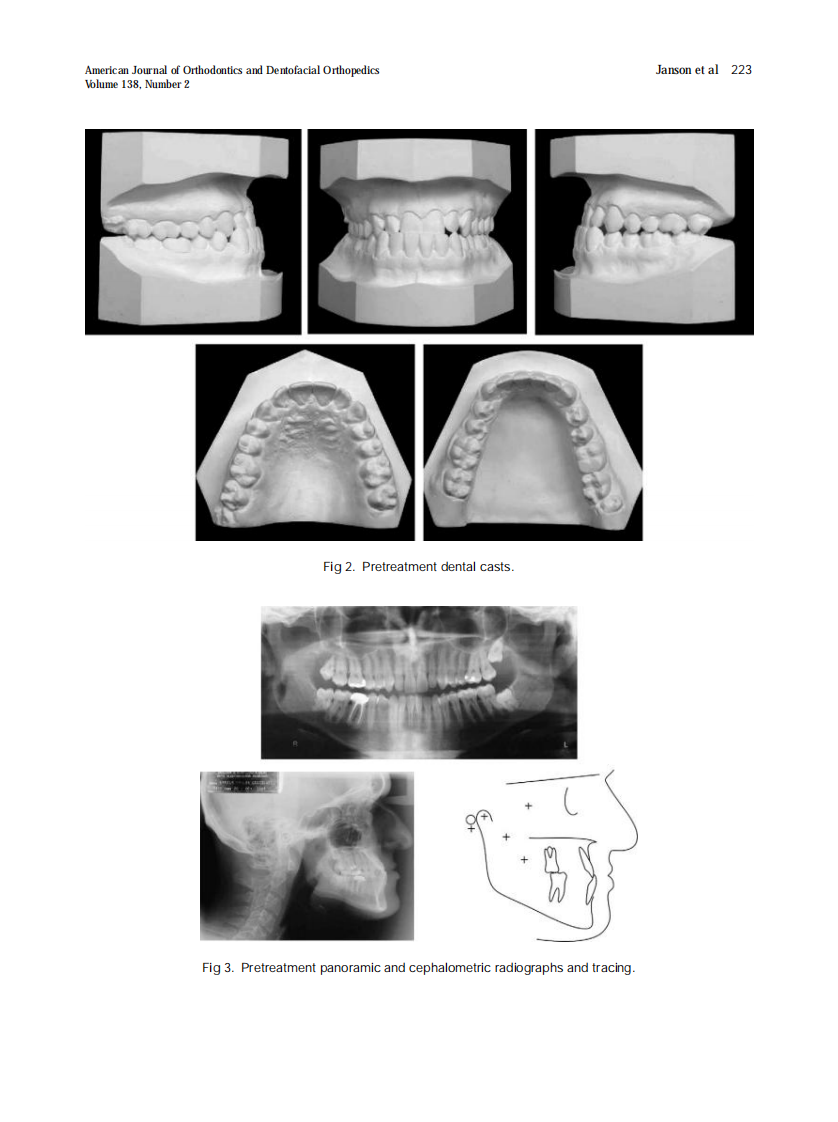

AJO-DO

2010_138_2_221_230.pdf